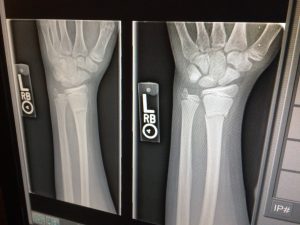

Ein Tätigkeitsschwerpunkt der Praxis ist die Behandung akuter Verletzungen. Werden Verletzungen in der Akutphase nicht sachgerecht behandelt, kann es zu dauerhaften Schäden kommen, die unter Umständen Korrektureingriffe erforderlich machen können Die häufigsten Verletzungen, die bei uns behandelt werden, sind: – Weichteilverletzungen – Knochenbrüche.

Die Röntgendiagnostik gehört zu den häufig angewandten Untersuchungen in der Unfallchirurgie und Orthopädie.